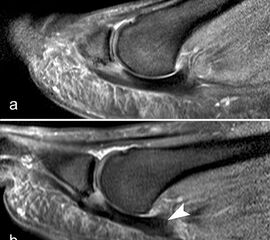

Rupturen ereignen sich am häufigsten an den distalen Insertionen der Metatarsophalan­gealgelenke (Abb. 5), etwas seltener auf Höhe der Metatarsaleköpfchen. Die Läsionen können sehr umschrieben sein, quer durch die gesamte plantare Platte reichen und sich sogar bis in die Kollateralbänder fortsetzen 1. Rupturen der plantaren Platte finden sich am häufigsten an der zweiten Zehe, die dritte Zehe ist etwas seltener betroffen. An der vierten und fünften Zehe sind die Läsionen sehr ungewöhnlich. Rupturen der pantaren Platte führen häufig zu einer ausgeprägten Weichteilreaktion, die nicht als Morton-Neurom fehlgedeutet werden sollte (Abb. 6) und zur Ausbildung einer Neo-Bursa führen können (Abb. 7).

Ein Sonderfall stellt die Großzehe dar: Hier verstärken die Sesambeine, das intersesamoidale und die sesamophalangealen Bänder die Gelenkkapsel. Der faserknorpelige Anteil der plantaren Platte distal der Sesambeine ist oft nur sehr dünn. Verletzungen dieser plantaren Kapselstrukturen des Großzehengrundgelenkes werden auch als „turf toe“ bezeichnet

(Abb. 8).

Die sagittalen PD FS Schichten im medialen und lateralen Bereich der plantaren Platte (a, c) zeigen eine völlig unauffällige,  Der kleine Flüssigkeitseinschluss in der Mittellinie der Zehe (b, Pfeil) entspricht einem physiolo

Zwischen der plantaren Platte und der Grundphalanx ist in der Mittellinie des Gelenkes ein kleiner Rezessus vorhanden (Abb. 9).

Dieser flüssigkeitsgefüllte Raum darf nicht als Ruptur der plantaren Platte fehlinterpretiert werden 23. Verletzungen der plantaren Platte erfassen immer auch den medialen oder lateralen Zügel.